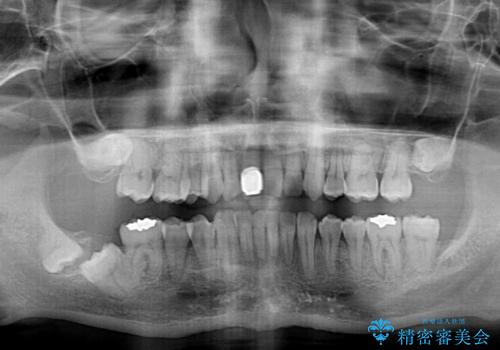

- ぶつけて前歯が折れてしまったとのことで来院された患者様です。

折れてしまった前歯は軽傷であり、歯内の歯髄に影響は及んでいませんでした。

通常では速やかにオールセラミッククラウンにて補綴治療を行うのですが、デコボコしている歯列も気になっていたため、事前に矯正治療を行うこととしました。

上顎歯列の叢生が著しかったため、上顎左右第一小臼歯2本を抜歯し、目立たないワイヤー装置にて治療を進めることとしました。

矯正治療後にはオーダーメイドタイプのオールセラミッククラウンを装着し、自然な口元に仕上がりました。